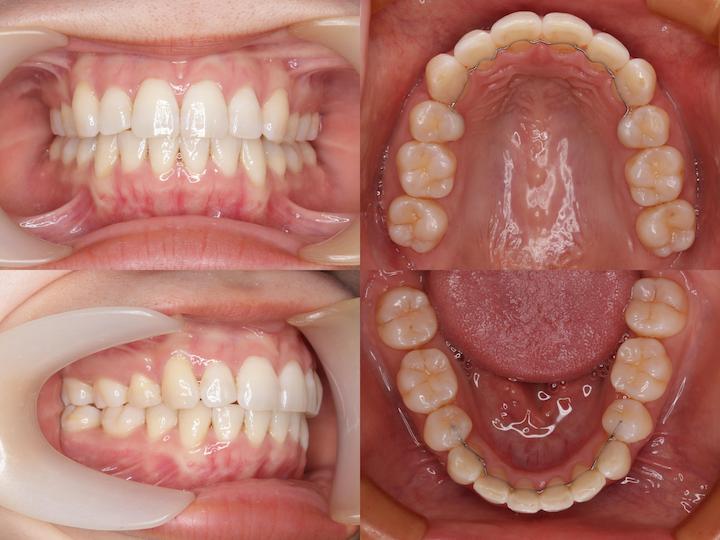

治療結果

叢生と口元の突出感が改善され、良好な咬合状態が得られました。費用